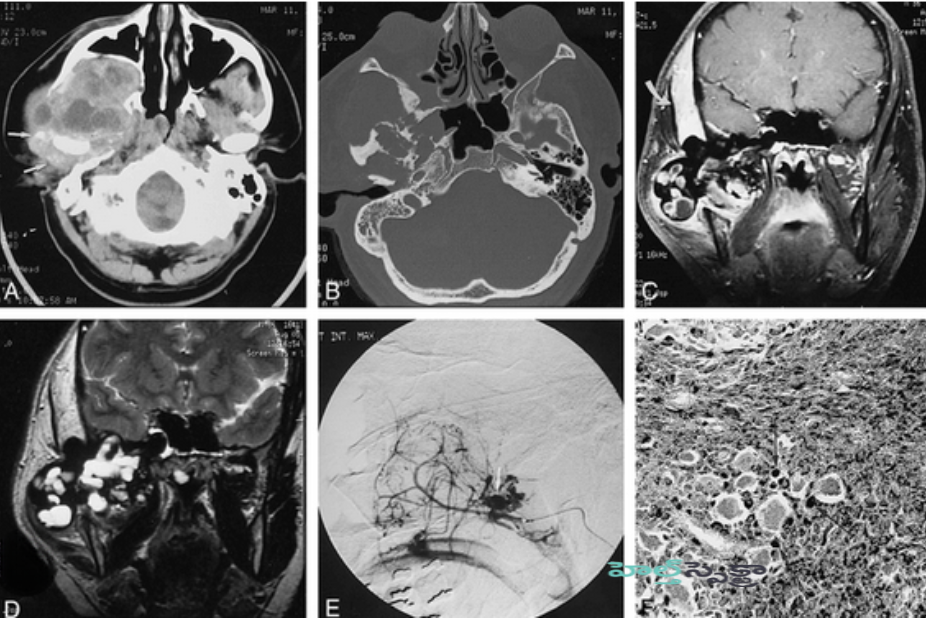

- ఎమ్మారై MRI: ఈ ఊహాత్మక పరీక్ష అవయవాలు, రక్త నాళాలు మరియు స్నాయువులు వంటి మృదు కణజాలం యొక్క స్పష్టమైన చిత్రాలను చూపుతుంది. మీకు స్థానికీకరించిన PVNS ఉంటే, అది ద్రవ్యరాశిగా కనిపించవచ్చు. మీకు డిఫ్యూజ్డ్ PVNS ఉంటే, అది మొత్తం కీలు లైనింగ్ గట్టిపడటం లేదా ఎముక మరియు మృదులాస్థి దెబ్బతిన్న ద్రవ్యరాశిని చూపించవచ్చు.

- ఎక్స్-రే X-ray: PVNS ప్రారంభ దశలో ఉంటే (అది ఎముకకు నష్టం కలిగించని చోట), కణితి ఎక్స్-రేలో కనిపించకపోవచ్చు. అయితే, ఎక్స్-రే మీ వైద్యుడికి ఆర్థరైటిస్ మరియు ఇతర ఆరోగ్య సమస్యలను తోసిపుచ్చడానికి సహాయపడుతుంది.